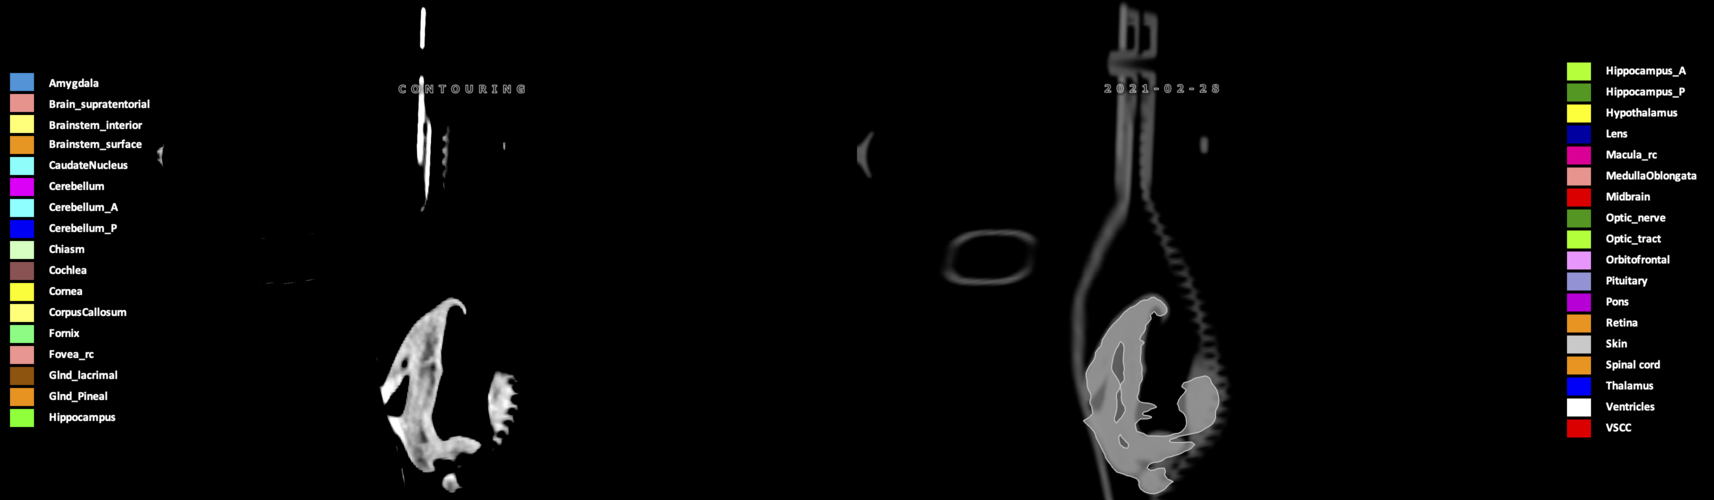

Eekers et al. have published an international neurological atlas for contouring of organs at risk in consensus with the European Particle Therapy Network (EPTN) in 2018 and an update in 2021. The purpose of this consensus atlas is to decrease inter- and intra-observer variability in delineating OARs relevant for neuro-oncology.

Included are all OARs known to be relevant for radiation-induced toxicity in neuro-oncology: brain, brainstem (midbrain, pons, medulla oblongata), chiasm, cerebellum (anterior & posterior), cochlea, cornea, hippocampus (anterior & posterior), hypothalamus, lens, lacrimal gland, optic nerve, pituitary, skin, and vestibular & semicircular canals. To further facilitate research on cognition, vision and radiological changes after irradiation of the brain, potential clinically-relevant OARs are included: amygdala, caudate nucleus, cerebellum (anterior & posterior), corpus callosum, fornix, macula, optic tract, orbitofrontal cortex, periventricular space (PVS), pineal gland, and thalamus.

We propose this atlas is used in photon and particle therapy in order to derive consistent dosimetric data. When required this atlas will be updated according to new insights.

Three-dimensional delineation of the 25 consensus OARs for neuro-oncology are shown on CT (WW/WL 120/40, 3000/600), 3T MR images, (T1Gd, T2FLAIR 1mm) and 7T MR (MP2RAGE 0.7 mm). All are presented in transversal, sagittal and coronal view.